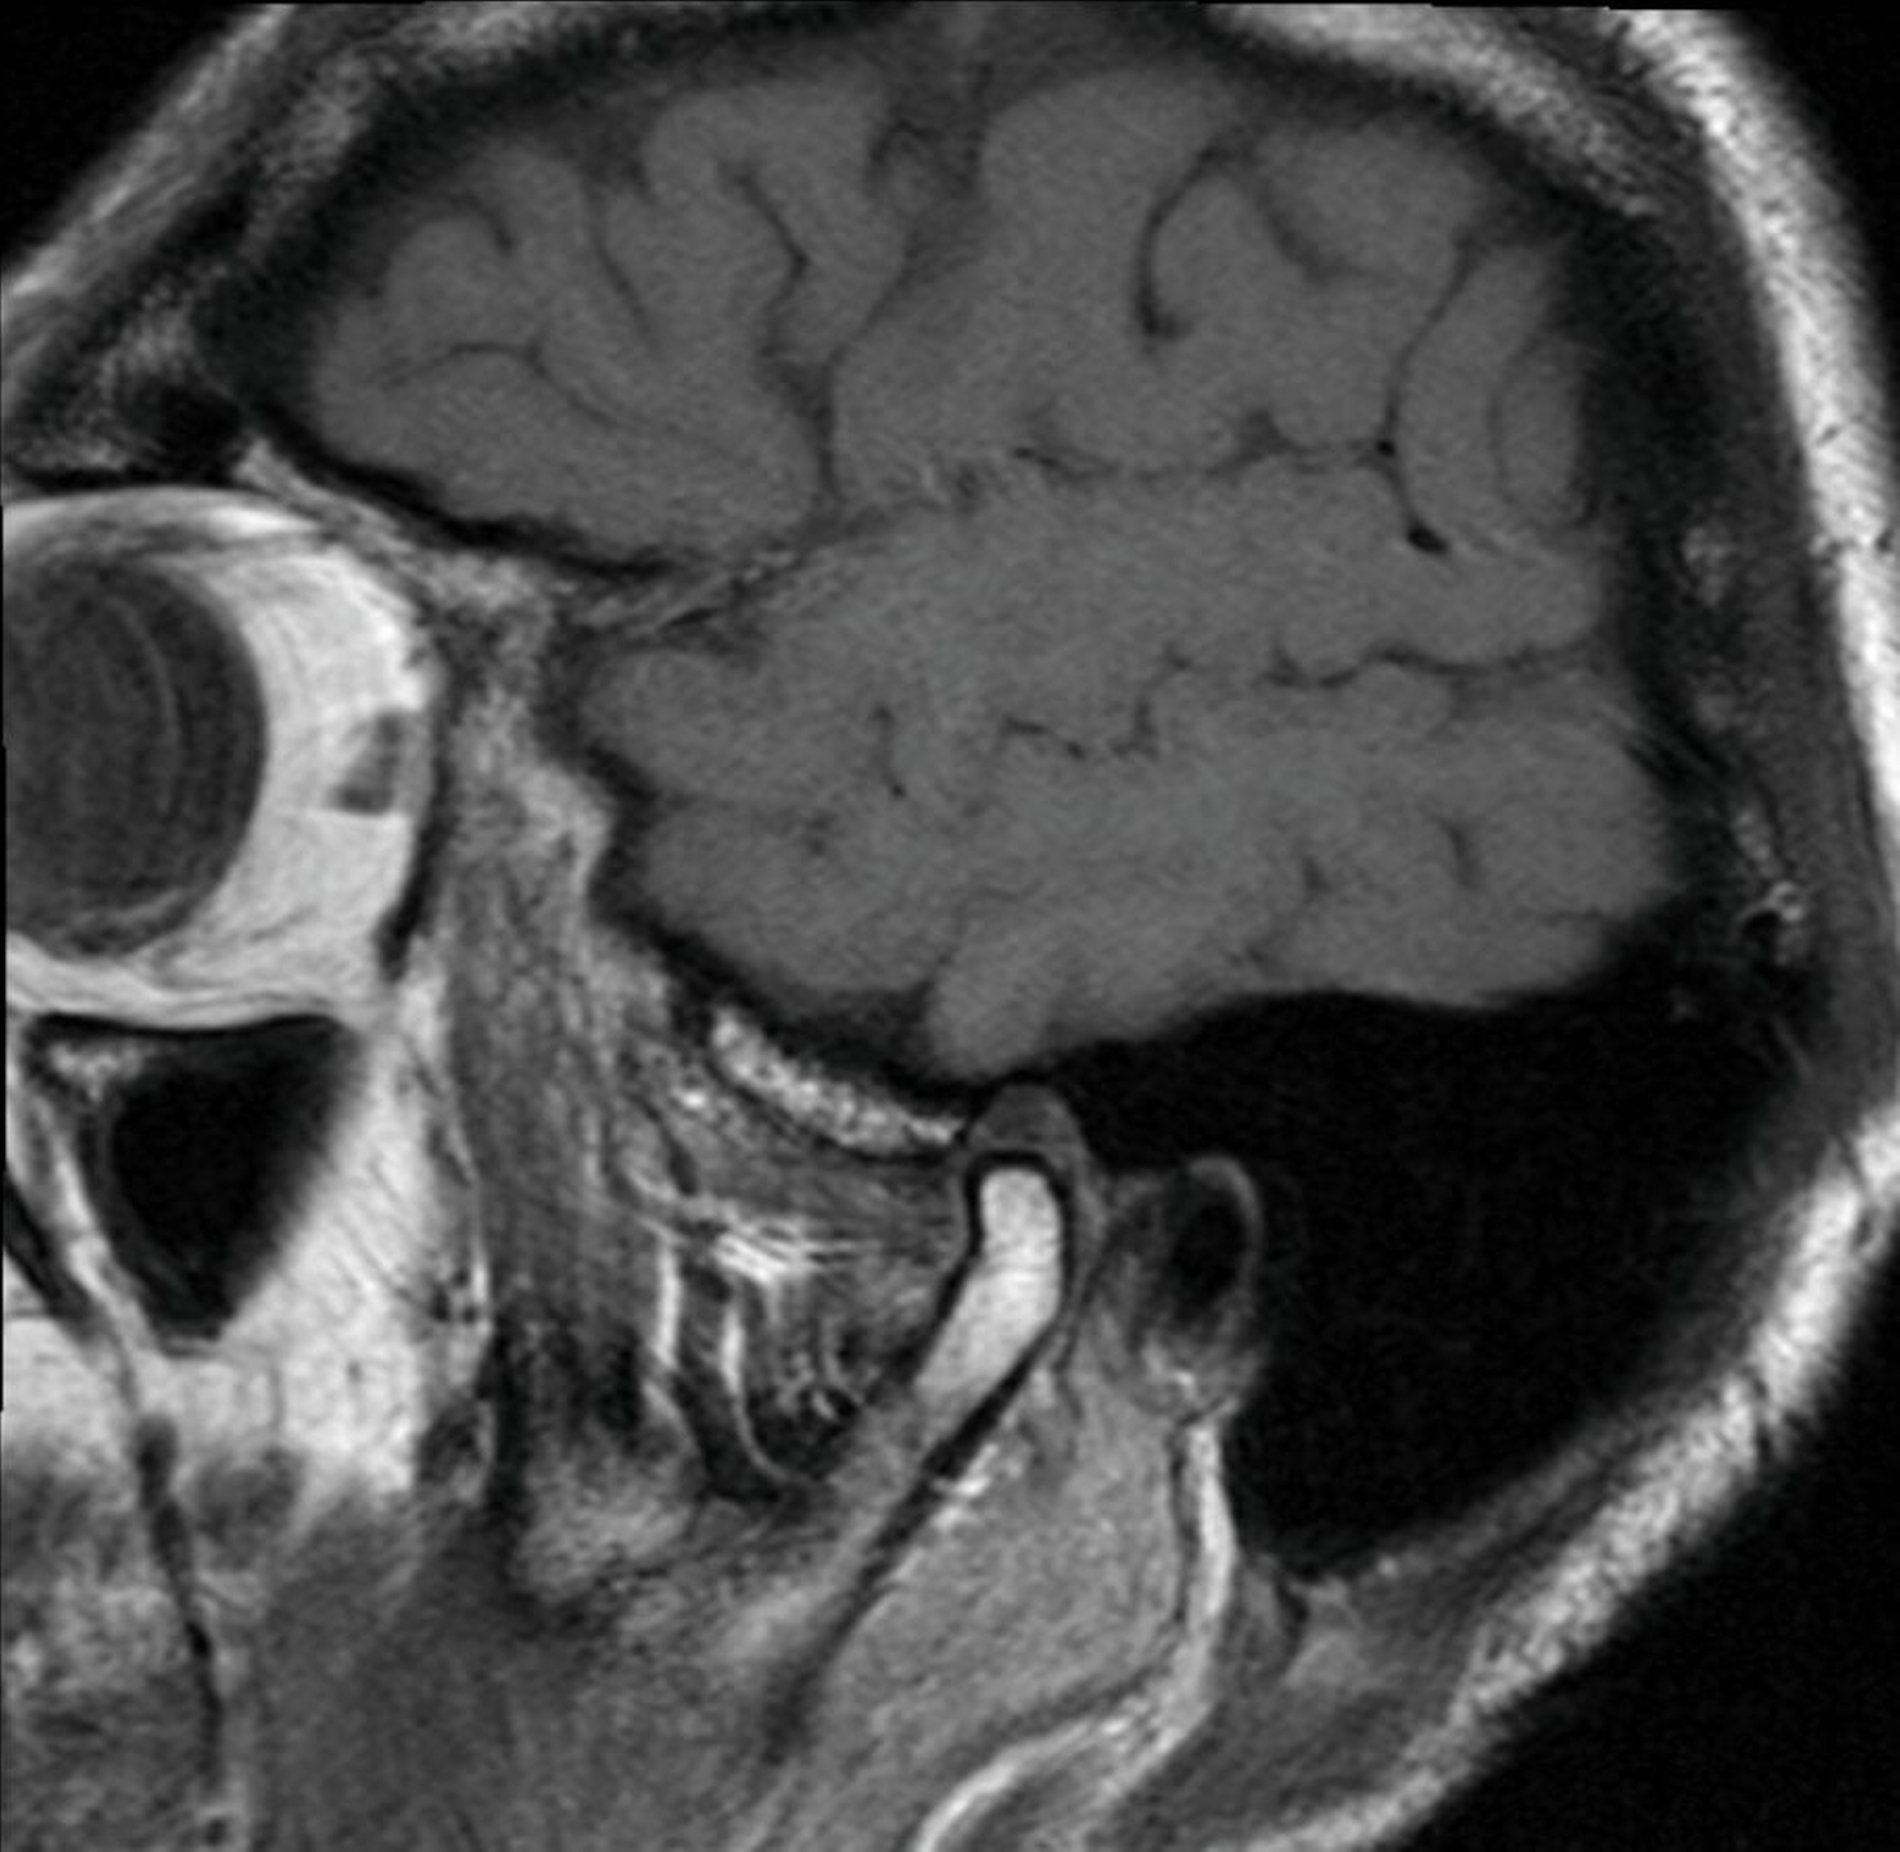

Bei der klinischen Inspektion zeigt sich eine erythematöse, narbig imponierende Hautveränderung präauriculär im Bereich der Kiefergelenke beidseits. Zusätzlich waren eine Hyperkeratose und eine schuppige Komponente zu erkennen (Abbildungen 1 und 2). Auf Palpation zeigte sich der präauriculäre Bereich auf Höhe der Kiefergelenke druckdolent. Während der Funktionsdiagnostik war der rechte Condylus mandibulae deutlich hypermobil. Knack- oder Reibegeräusche waren nicht zu hören. Gleichzeitig war eine Deviation zur linken Seite bei der Mundöffnung zu beobachten. Die orale Mundschleimhaut erschien unauffällig bei Abwesenheit von Blasen oder Erosionen. In der alio loco angefertigten MRT-Aufnahme, die durch den Hauszahnarzt entsprechend der aktuellen Literatur [Schmidt et al., 2022; Neff, 2021] angefordert und vom Patienten mitgebracht wurde, zeigte sich die Struktur des Gelenks und des Diskus regelrecht (Abbildungen 3 und 4). In den Aufnahmen während der Kieferöffnung war lediglich eine Hypermobilität des rechten Condylus mandibulae zu erkennen (Abbildung 5). In der T1-Wichtung waren keine Infiltrationen oder entzündliche Veränderungen des präauriculären Weichgewebes zu sehen.